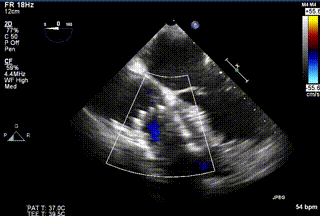

2021年12月24日,復(fù)旦大學(xué)附屬中山醫(yī)院葛均波院士團(tuán)隊成功應(yīng)用LuX-Valve Plus為一例極重度三尖瓣反流(TR)合并房顫、房缺的患者完成了經(jīng)血管三尖瓣置換術(shù),這是在前基礎(chǔ)上,本周完成的第三例經(jīng)血管三尖瓣置換手術(shù),葛均波院士、周達(dá)新教授等與心外科魏來教授、賴顥教授,心超室的潘翠珍教授、李偉教授及麻醉科的郭克芳教授共同完成了本周手術(shù),均獲得圓滿成功!患者術(shù)后超聲顯示無TR,臨床癥狀明顯改善。本周手術(shù)的成功也為LuX-Valve Plus救治性臨床研究添上了濃墨重彩的一筆。

三例患者入院后,葛均波院士團(tuán)隊周達(dá)新教授、潘文志教授、張源博士、陳莎莎博士及心超室的潘翠珍教授、李偉教授對患者的情況進(jìn)行詳細(xì)評估和討論,最終決定為三例患者選擇LuX-Valve Plus40mm、50mm和50mm型號的瓣膜進(jìn)行手術(shù)治療。手術(shù)后即刻拔除氣管插管,術(shù)后患者三尖瓣反流癥狀得到顯著改善,復(fù)查心超結(jié)果顯示人工三尖瓣瓣膜支架固定穩(wěn)定,瓣葉關(guān)閉形態(tài)未見異常,未見明顯反流。